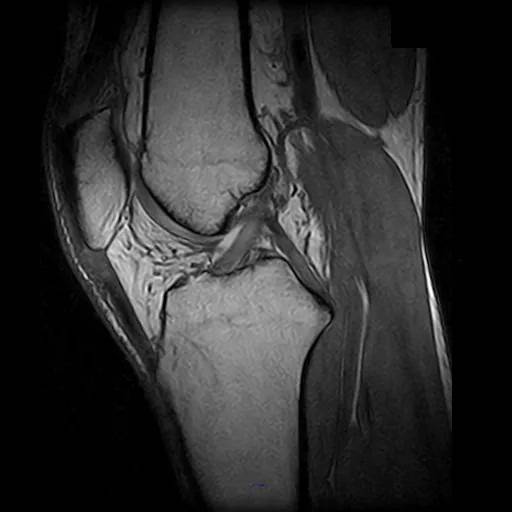

閉所が苦手でも大丈夫。圧迫感がなく、リラックスした状態で検査を受けられます。 - 整形外科領域に特化した高画質診断

肩・腰・膝の痛みに、的確な診断を。関節や脊椎の診断に特に適しており、詳細な画像で原因をはっきり診断できます。 - 騒音が少なく快適な検査環境